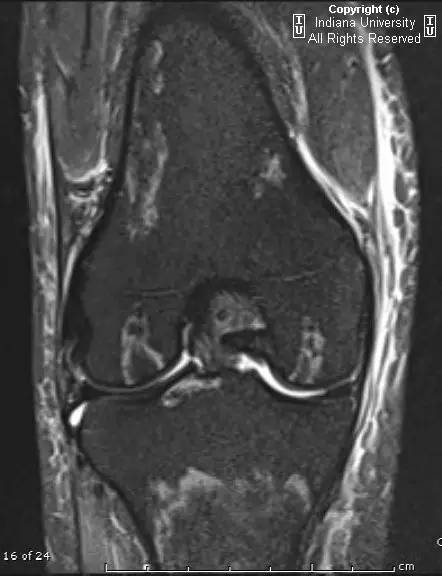

- 膝关节MRI:双侧膝关节股骨干骺端、股骨髁、胫骨干骺端、髌骨T1信号减低、T2信号增高,股骨髁关节面也有类似的信号异常。软组织弥漫性水肿。同时存在关节积液。

【诊断】缺血性坏死(AVN)及骨梗死

- AVN表现为软骨下局部缺血并骨髓水肿。骨梗死表现为松质骨内匐行性的边界或轮廓病变。

- MR骨梗死示不规则或匐行性T1低信号、T2高信号,周围骨髓水肿。AVN表现为软骨下T1信号减低、T2信号增高,伴水肿和关节面塌陷。